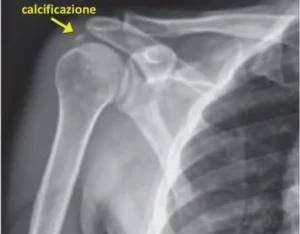

La litoclasia percutanea è un metodica mini-invasiva utilizzata per il trattamento di grossolane calcificazioni che spesso si formano all’interno dei tendini della spalla, dando origine a un processo infiammatorio definito tendinite calcifica, causa di dolore e importante limitazione nei movimenti articolari.

La “litoclasia” consiste in un vero e proprio lavaggio della calcificazione con soluzione fisiologica, iniettata all’interno della calcificazione tramite uno o due aghi (opportunamente inseriti sotto monitoraggio ecografico) e che letteralmente “scioglie” il calcio, in modo da poter essere drenato attraverso gli stessi aghi